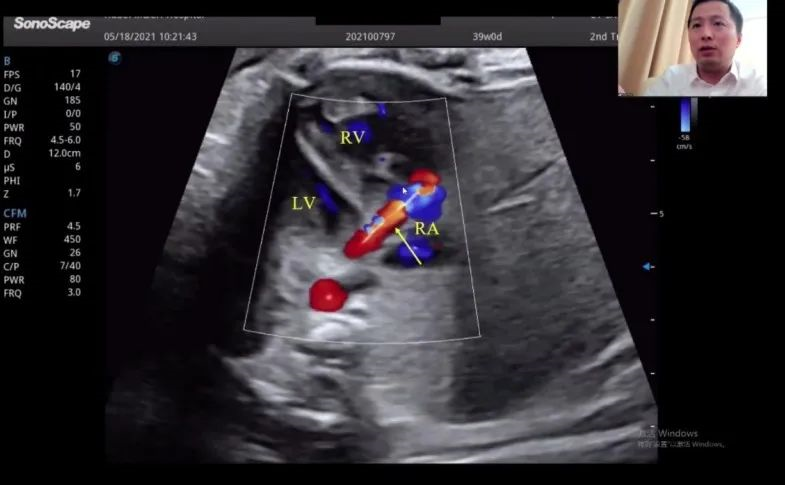

浙江大學(xué)醫(yī)學(xué)院附屬邵逸夫醫(yī)院的趙博文教授聚焦先天性心臟疾?。–HD)的產(chǎn)前診斷,通過(guò)特殊病例的展示講解,包括法洛四聯(lián)癥(TOF,一種常見(jiàn)的先天性心臟畸形)的時(shí)空關(guān)聯(lián)成像技術(shù)(Spatio-Temporal Image Correlation,STIC)、大動(dòng)脈完全轉(zhuǎn)位(cTGA)和右心室雙出口(DORV)的圖像,前瞻性地提出智能胎心的應(yīng)用場(chǎng)景。“胎心檢查人工智能的應(yīng)用非常有價(jià)值,能夠縮短檢查時(shí)間,提高臨床的診療效率,”趙教授如是說(shuō)。

湖北省婦幼保健院的趙勝教授在會(huì)上帶來(lái)了胎兒冠狀動(dòng)脈瘺超聲診斷研究的分享。趙教授表示,冠狀動(dòng)脈瘺在妊娠晚期可通過(guò)超聲檢查顯示出來(lái),經(jīng)線(xiàn)圈栓塞或冠狀動(dòng)脈瘺術(shù)后,進(jìn)一步的臨床過(guò)程通常較為順利。